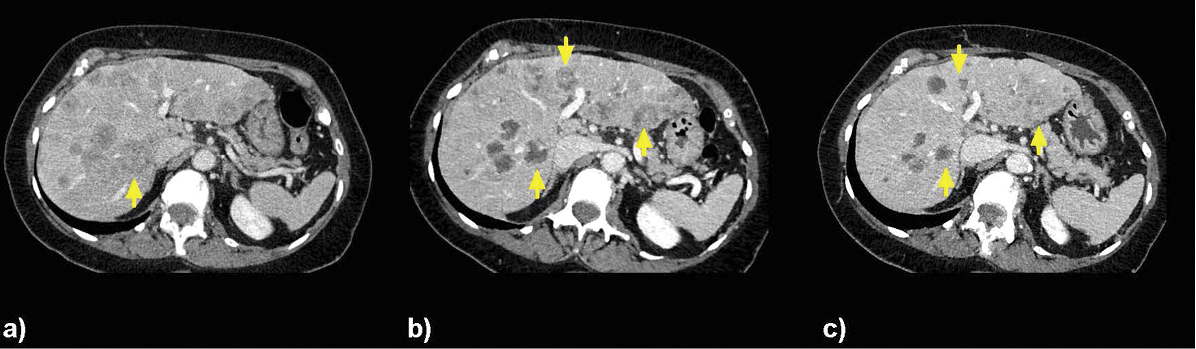

New research on the minimally invasive, image-guided therapy Yttrium-90 (Y-90) radioembolization shows promise in treating breast cancer that has spread to the liver when no other treatment options remain.

In research presented at the 2014 Society of Interventional Radiology Annual Meeting, Dr. Lewandowski and colleagues treated 75 women (ages 26-82) with breast cancer liver metastases, all of whom had progressive disease. In addition, 85 percent of these women had multiple liver tumors and 77 percent had disease outside the liver.

Researchers determined that the tumors got smaller or remained stable in 98.5 percent of the patients after radioembolization, while tumor reduction of more than 30 percent occurred in 24 patients. Additionally, these women experienced no major side effects.

In Y-90 radioembolization, an interventional radiologist guides a catheter into the hepatic artery that supplies blood to the liver. Microbeads containing radioactive Y-90 are then injected and float downstream to deliver cancer-killing radiation inside the heart of the tumor.